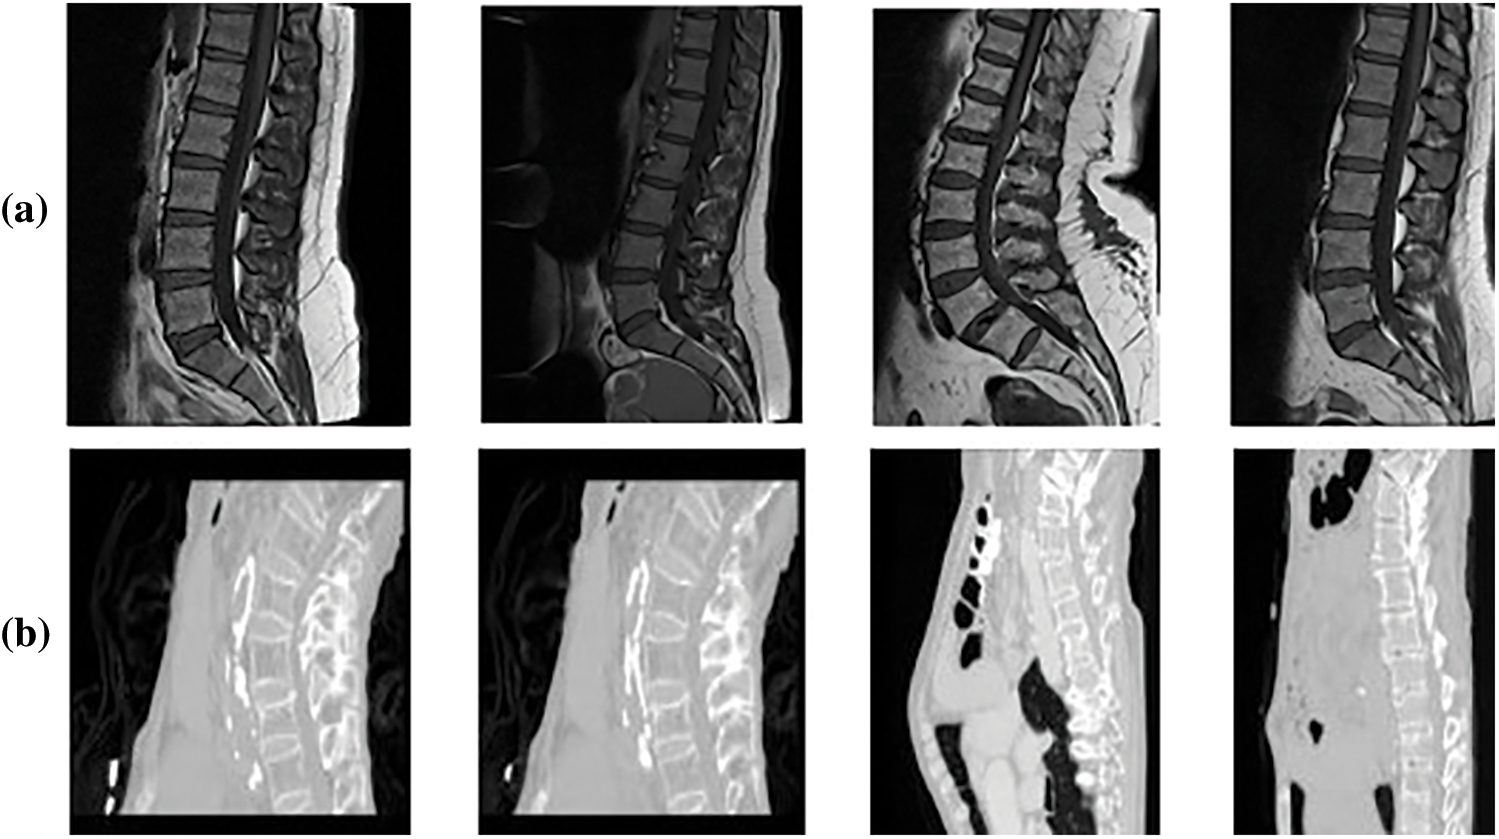

In this research, Mendeley and CSI 2016 datasets are utilized for the experimentation. Data-set details are discussed in this section. The Computational Methods and Clinical Applications for Spine Imaging (CSI) conducted a challenge and produced a dataset in the year 2016 of a sagittal view of lumbar spine CT images. The publicly available training data is divided into 2 splits of training and testing. Input images size is processed and set as 256 × 256. An expert radiologist examined the cases and manually marked the fracture sites [23]. Fig. 3 shows the original images of CSI 2016 datasets. Tab. 3 shows the dataset details with total number of images, along with its resolution. The division of training and testing images is also presented. Data augmentation involved noise addition, horizontal flip, rotation, shearing and cropping which increased the total number of images. For data labelling LabelMe and Roboflow tools were used. The naming convention of labelled images as set the same as original images.

Figure 3: Sample dataset images (a) Mendeley MRI scans (b) CSI 2016 CT scans

This data was published in 2019 with the contribution of [24], containing MRI scans of 575 patients who have symptomatic back pain in sagittal or axial view. The dataset was provided with the support of Universitas Multimedia Nusantara, Liverpool John Moores University. There are a total of 48,345 MRI slices in this dataset with an image resolution of 320 × 320 and 320 × 310 respectively. The image format of MRI scans is .png. Before use images are resized to 416 × 416. Total 514 images were selected and 61 were discarded.

5th International Workshop and Challenge, held in Conjunction with MICCAI 2018, Granada, Spain, September 16, 2018 [25]. CSI2016 dataset has 25 thoracolumbar spine CT scans acquired at a resolution of between 1 and 0.35 mm with Hologic Discovery A DXA scanner, the images are provided in both bmp and .vtk formats with total of 303 scans.